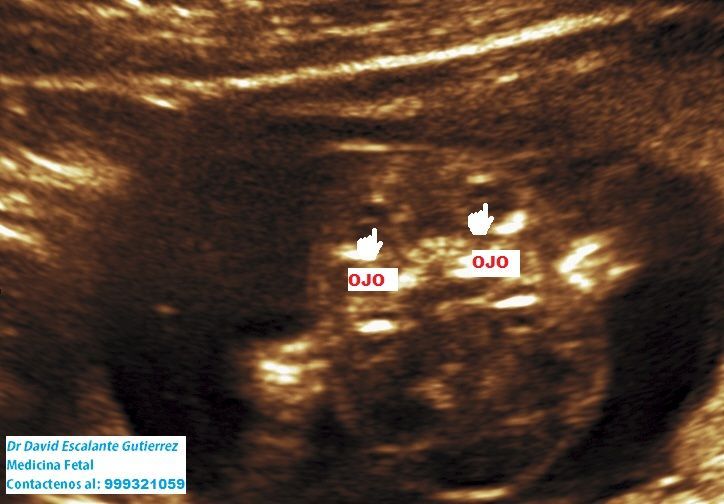

Realizamos las ecografías de viabilidad del embarazo, genética, morfológica, de bienestar fetal, ecocardiografías fetales, así como procedimientos invasivos como biopsia de vellosidades coriales y amniocentesis.